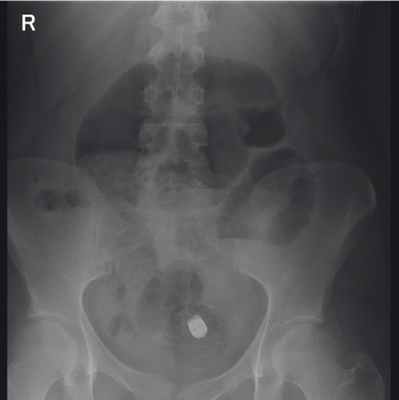

Во время пребывания пациентки в стационаре отхождение капсулы не зафиксировано. Подобные случаи задержки капсулы у пациентов с болезнью Крона и поражением тонкой кишки известны. Как правило, после назначения больным противовоспалительной терапии, когда благодаря спаданию отека слизистой оболочки просвет кишки восстанавливается, наблюдают дальнейшее продвижение капсулы и ее благополучный выход. Однако в данном случае после курса терапии месалазином капсула не отошла. По данным КЭ, на уровне ее ретенции визуализировались участки воспаленной слизистой оболочки подвздошной кишки со стриктурой. Учитывая отсутствие клинических признаков кишечной непроходимости, пациентка в удовлетворительном состоянии была переведена на амбулаторный режим. В октябре 2015 г. больная повторно поступила в отделение воспалительных заболеваний кишечника с ухудшением состояния (нараставшими болями в правых отделах живота, тошнотой, рвотой), была выполнена обзорная рентгенография органов брюшной полости, по результатам которой капсула визуализировалась в подвздошной кишке, определялись горизонтальные уровни жидкости ( рис. 5 ).